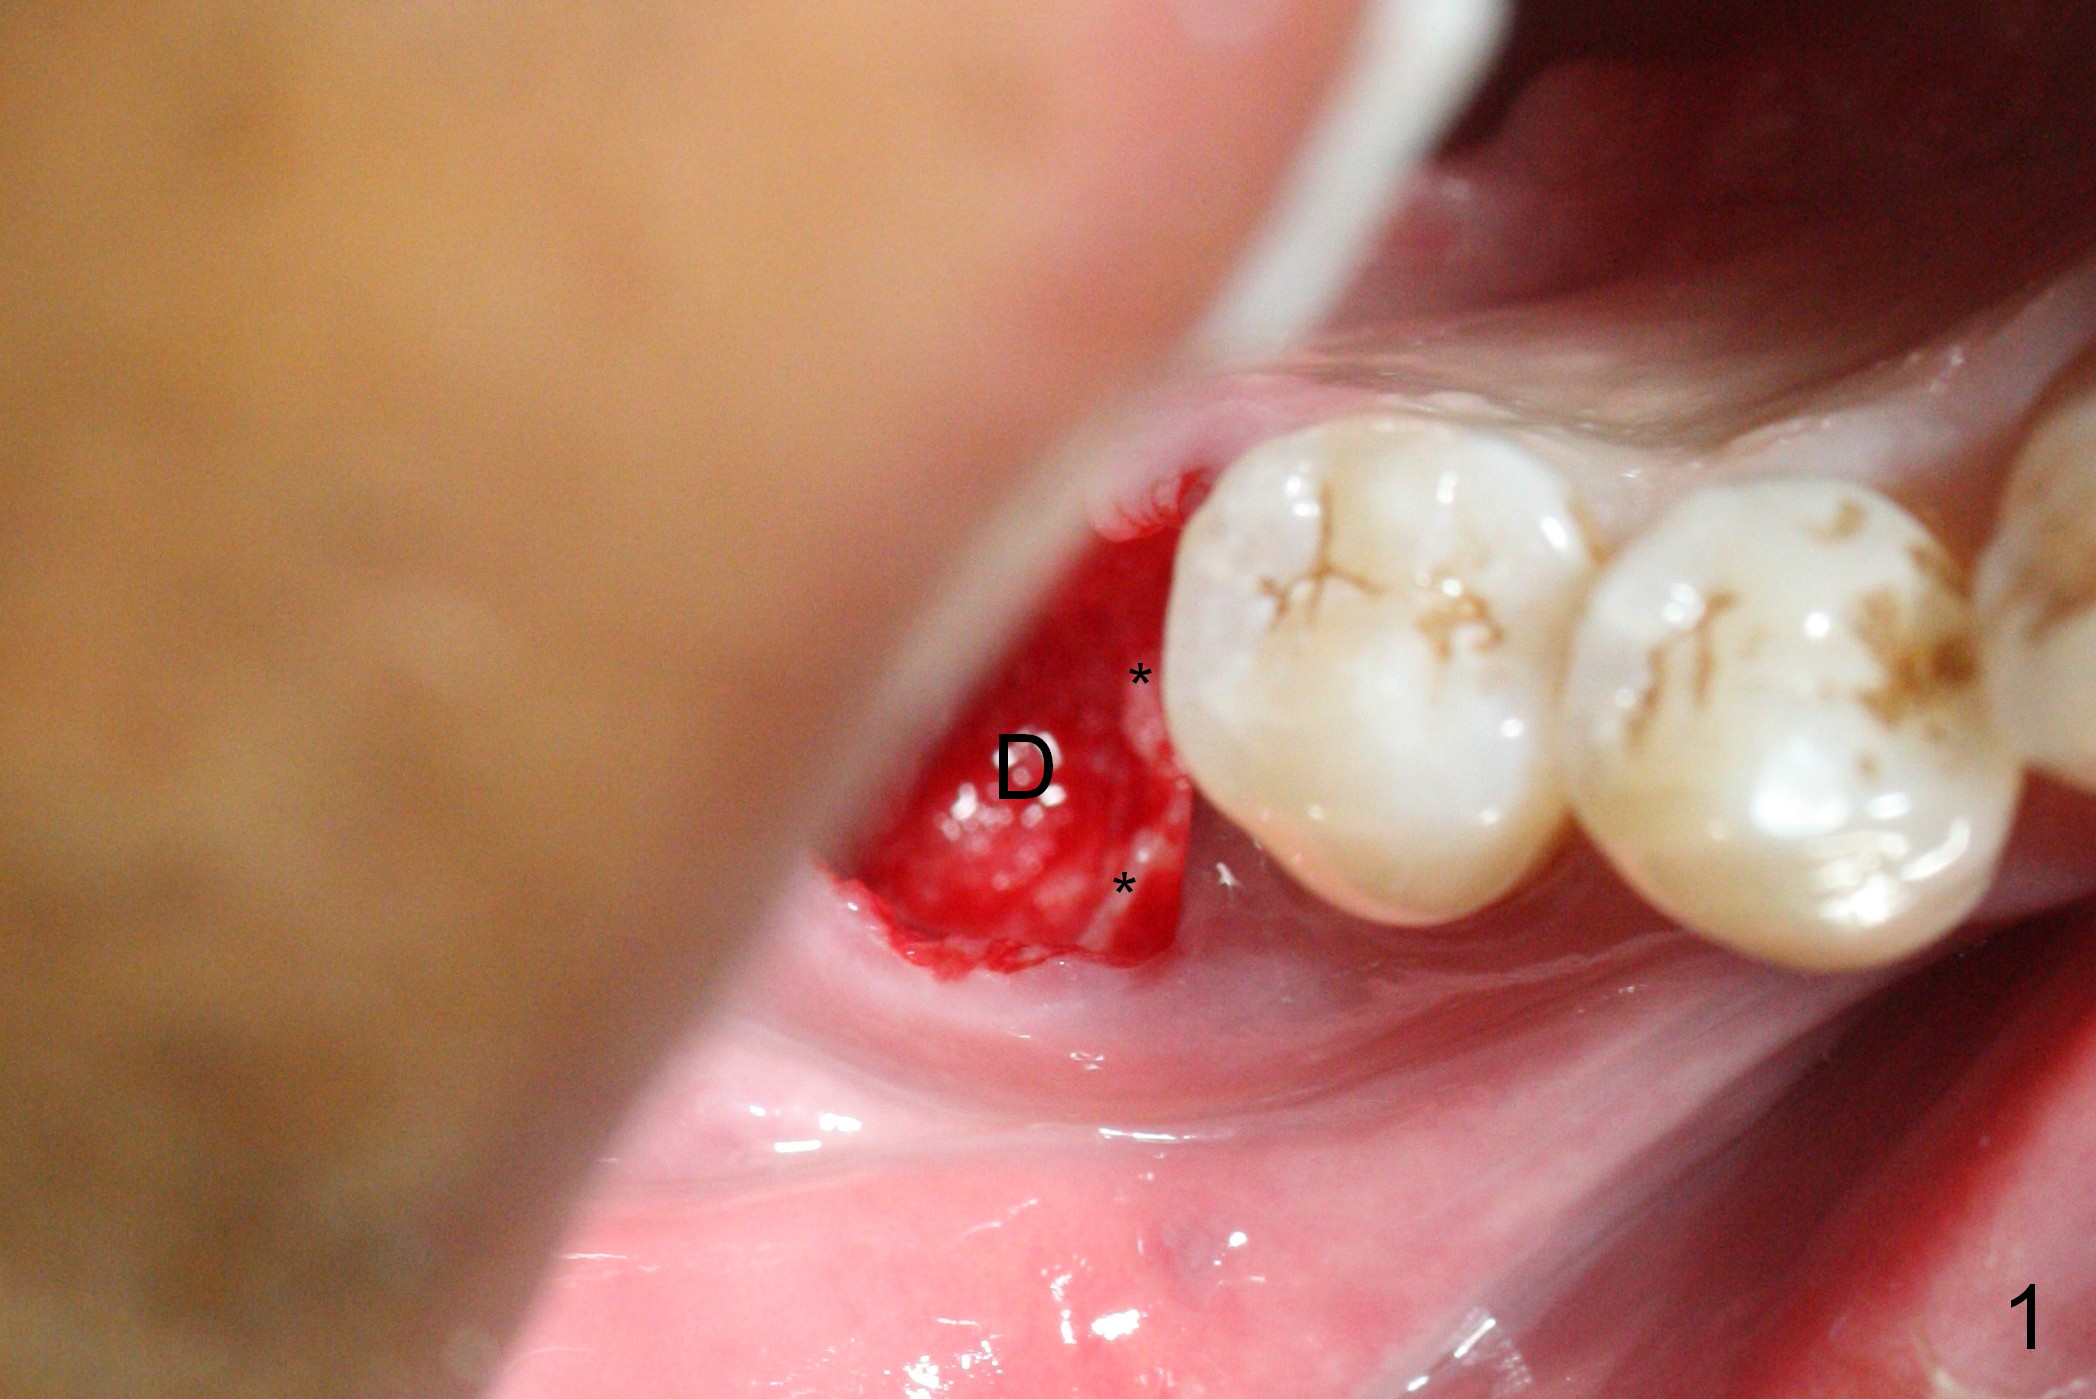

Extraction shows the large distal socket (Fig.1 D) and the thin and low septum (*) of the tooth #30. After Magic Split test confirms hard bone, osteotomy is initiated with 1.6 mm pilot drill with 11 mm stopper (Fig.2); there is 2.7 mm distance to the Inferior Alveolar Canal. Following Marking Bur, a 4.8 mm Magic Drill is used to finish the osteotomy with difficulty because of hard bone and ineffective local anesthesia due to infection. A 5x9 mm "dummy" implant is placed to determine the placement level relative to the distal crest (Fig.3 *). After removal of the dummy implant, an authentic one with the same dimension is placed with packing abundant allograft (.5-1.5 mm) and Osteogen (Fig.4 *); it appears that 4 to 5 threads (fins) of the implant (arrowheads) are engaged to the native bone for primary stability (>40 Ncm). Later more bone graft is placed distally (Fig.5 arrow). With the short implant placed not so deep, there is 6-7 mm clearance from the underlying canal (Fig.6). The patient is doing well 7 days postop (Fig.7). He feels that the provisional is too bulky buccally for the first 2 days postop. The buccal margin will be trimmed in another 2 weeks (dashed line). The patient in fact masticates on the right side postop. By the time he returns for provisional revision 1 months 10 days postop, he has mild pain. There is food entrapment. The provisional and the abutment are slightly loose, whereas the implant is stable with healing socket (Fig.8). A healing abutment is placed. The implant appears unstable nearly 5.5 months postop. The gap between the bone and implant seems to be large (Fig.9). The implant should have been larger and longer for fast healing. A healing screw is used instead. The site heals 10 months postop with an increase in bone density around the implant (Fig.10.) Prior to cementation of the final crown, the abutment is minimally exposed (Fig.11 (6.5x5.7(3) mm)). In fact the abutment screw becomes loose 2 months post cementation (1 year postop); it appears that crown/implant ratio is unfavorable (Fig.12). The implant is slightly placed mesially (cantilever). The patient cannot chew on the left. The tooth #19 is periodontally affected and the tooth #18 is missing. When bone loss is severe, the implant should be as large as possible and preferably tissue-level. The abutment screw is re-loosening 1.5 years post cementation (4 months post #19 socket preservation, Fig.13). The crown/implant ratio at #31 is more favorable than that at #30 (compare black lines). The crown at #31 has large contact area with the tissue-level implant (external), whereas the contact between the abutment and the bone-level implant is much less (internal). To prevent the abutment screw re-loosening (turning) in function, a screw driver (Fig.14 D) will be buried inside the crown/abutment after the screw is retightened. Make sure that the driver is in the middle of the access hole. Section the driver in situ obliquely (Fig.15); flat sectioning allows the driver to turn with the abutment screw in function. After insertion of plumber tape around the sectioned screw driver, use composite to fix the driver in place and seal the access hole (Fig.16). Occlusal check suggests weak link between the abutment and bone-level implant at #30.